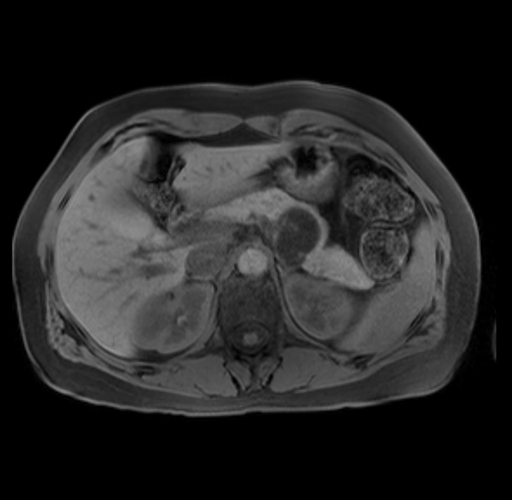

Imaging Analysis

Look through the patient's CT scan to identify any areas of concern for the necessary procedure.

Based on your CT findings, which issue(s) are present and would give reason for "planned slowing down moment(s)" in this case?